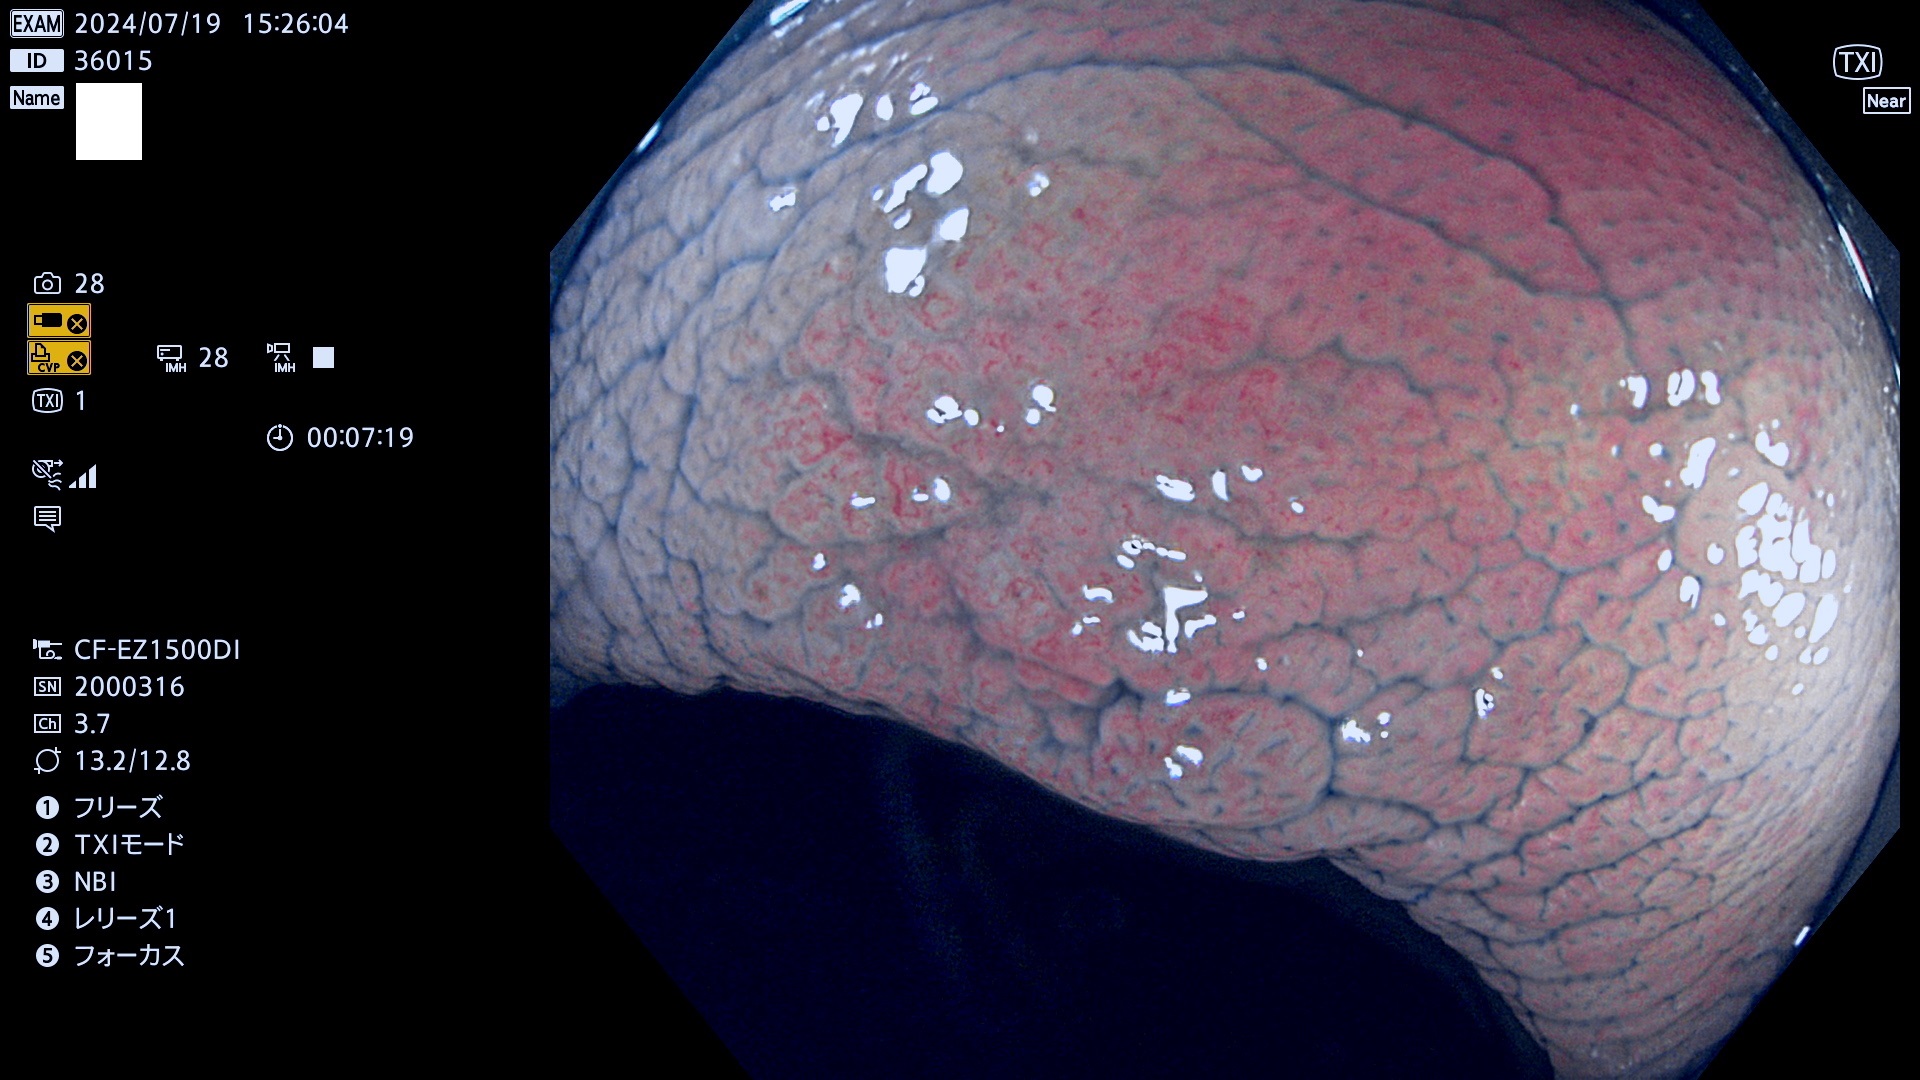

今週のUb、Uc型腺腫

完全に平坦な物をUb、陥凹している物をUcと呼びます。最も発見が難しく危険な病変です。

毎週の検査(木・金・土・日)に発見されたUb、Uc型・腺腫を、その週の日曜の夜にUPし1週間、提示します。

抽出の対象期間 2024年7月18日〜7月21の4日間(25件の検査)6件 (6/25=24%)